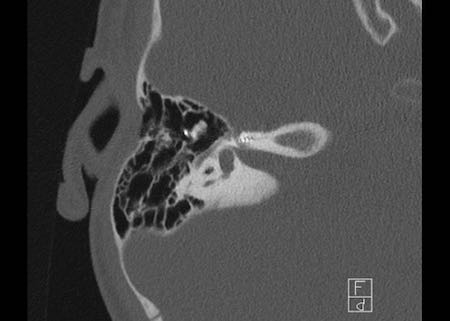

Bên trái là hình ảnh của một bé gái 2 tuổi.

Các hình ảnh từ kết quả chụp CT được thực hiện trước khi cấy ốc tai điện tử.

Quan sát thấy dị dạng nhẹ ở đỉnh ốc tai – không có sự phân tách giữa vòng thứ hai và vòng thứ ba, và trụ ốc tai xương vắng mặt.

Cống tiền đình bình thường.